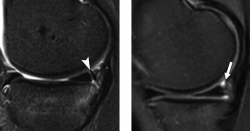

The first image shows far peripheral longitudinal meniscal tear on sagittal T2-weighted fat-suppressed image in an 18 year-old boy with anterior cruciate ligament–deficient knee. The second image shows a normal meniscocapsular junction in a 17 year-old girl. The arrow points towards a normal meniscocapsular recess.